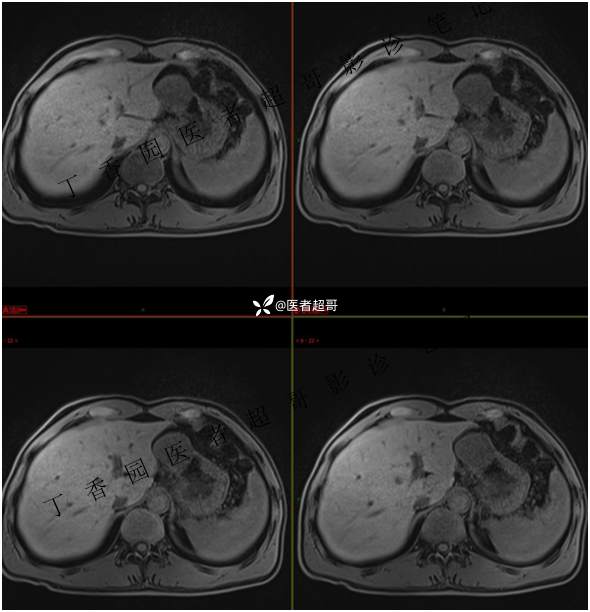

肝胃间隙肿瘤,间质瘤?平滑肌瘤?还是鞘瘤?有结果,请分析!

现病史:患者于3天前查体行肝胆脾胰肾彩超示肝内实性占位,无恶心、呕吐,无发热、寒战,无腹胀、腹泻,进一步于医院行上腹部CT增强示:肝胃交界处肿块。未行特殊治疗。今患者为求进一步治疗,来我院就诊,门诊以“肝占位性病变”收入院。患者自发病以来,神志清,精神可,饮食睡眠可,二便可,体重近期未见明显变化。